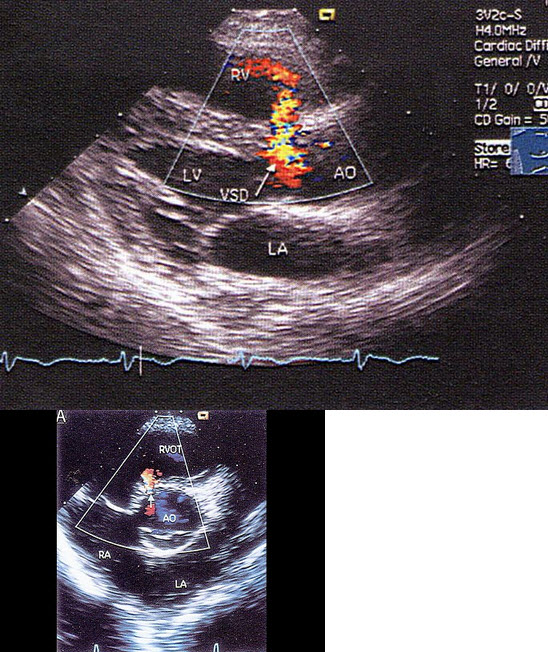

室间隔膜部缺损

室间隔缺损,以上室间隔缺损属于哪型()

心底短轴切面室间隔缺损分型 (转载)